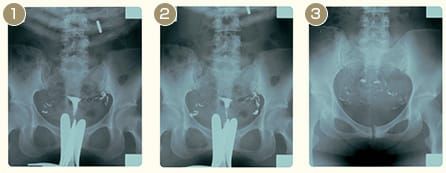

子宮卵管造影(HSG)

- 子宮から造影剤を注入。左右の卵管を造影剤が通過しているのがわかる

- その後、卵管采から腹腔内へ造影剤が流出する

- 再びレントゲン撮影。造影剤がきちんと腹腔内で拡散していれば異常なし